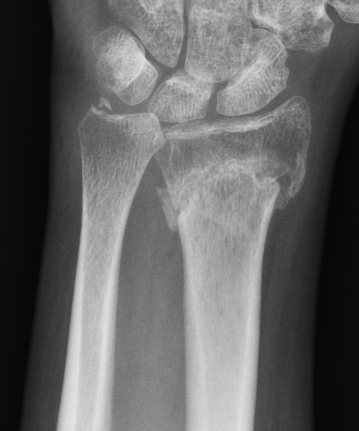

Xray

Bilateral xrays

PA film in neutral

- wrist neutral

- elbow & shoulder at 90°

CT

Malunion

| Radial shortening | Radial inclination | Positive ulna variance |

| Dorsal tilt > 15 degrees | Volar tilt > 10 degrees | Articular step > 3 mm |